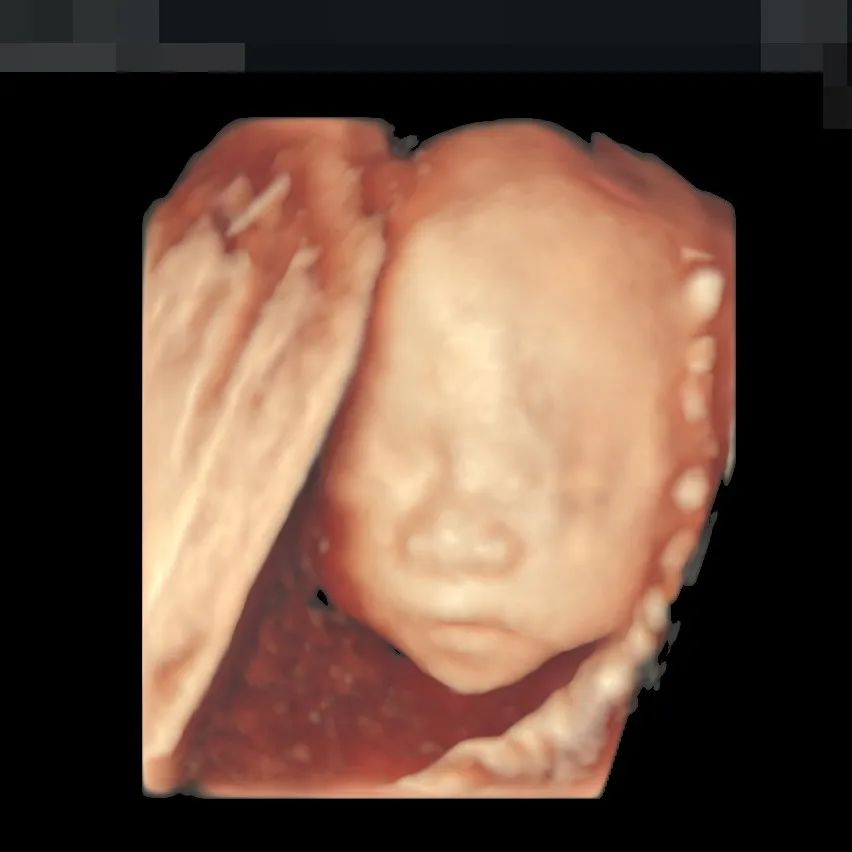

重度肥胖、肚皮脂肪层厚,对超声医生的技术和筛查仪器都是考验。但正是这类准妈妈,患有妊娠合并症或并发症的几率会更高,孕中期超声筛查对她们而言有着更重要的意义。

我们的医生也接触过很多大体重、双胎等复杂情况的孕妈,对此有着丰富的处理经验。对于这类孕妈,也会用更耐心、更负责的态度为她们筛查,守护宝宝健康发育、平安诞生。

▲190斤孕妈王女士,不仅做了全面筛查,还留下了宝贵的胎儿影像,全家人都非常满意